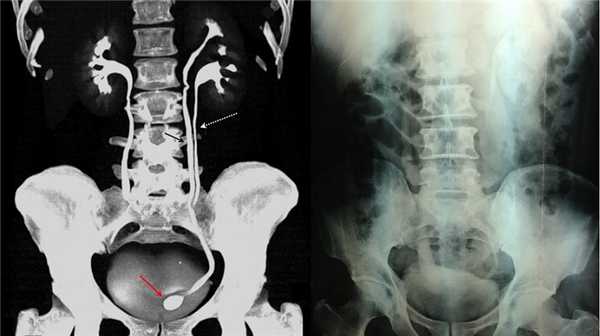

Рисунок. КТ-урография (1) показывает неполное удвоение ЧЛС слева: два мочеточника соединяются на входе в таз и единым мочеточником вступают в мочевой пузырь; внутрипузырная часть мочеточника расширена (красная стрелка) — уретероцеле. Уретероцеле хорошо видно на рентгенограммах (2) при экскреторной урографии: правый мочеточник расширен на всем протяжении, дистальный отдел кистозно расширен — «голова кобры».

Рисунок. Уретероцеле (стрелка) на УЗИ и КТ.

Обычно уретероцеле обнаруживают при обследовании пациента по поводу рецидивирующей инфекции мочевых путей. В общем анализе мочи обычно обнаруживают лейкоцитурию, эритроцитурию. При бактериологическом исследовании мочи находят рост микрофлоры. При ультразвуковом исследовании (УЗИ) почек можно обнаружить расширение чашечно-лоханочной системы почки и мочеточника на стороне поражения. При УЗИ мочевого пузыря уретероцеле выглядит как округлое тонкостенное образование с жидкостным содержимым, выступающее в полость мочевого пузыря. С помощью экскреторной урографии или компьютерной томографии с контрастированием можно получить объективную информацию о строении верхних мочевых путей, визуализировать уретероцеле, которое определяется как булавовидный дефект наполнения мочевого пузыря в проекции устья мочеточника. В профессиональной медицинской литературе существует рентгенологическое описание уретероцеле, как «головы кобры» или «гетманской булавы». Непосредственно осмотреть уретероцеле возможно при цистоскопии. В процессе обследования пациента с уретероцеле важно оценить функцию почки на стороне поражения. УЗИ почек и компьютерная томография позволяют также судить о размере почки и сохранности паренхимы почки по её толщине. Но наиболее достоверную информацию о выделительной функции почки может дать динамическая нефросцинтиграфия.